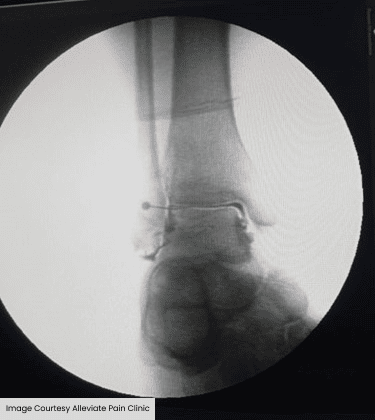

Fluoroscopy guided Platelet Rich Plasma injection of the ankle carried out under fluoroscopic guidance at Alleviate Pain Clinic, Bengaluru.

Inadequate bony healing is seen 9-week post op on x-ray

- Malunion occurs when fractured bones heal improperly, causing misalignment. Non-union refers to fractures that fail to heal altogether.

- Both conditions lead to altered biomechanics, abnormal stress on the ankle joint, and persistent pain.

- Symptoms include deformity, instability, swelling, and pain exacerbated by weight-bearing or physical activity.

- Common in cases of neglected fractures or inadequate surgical fixation.